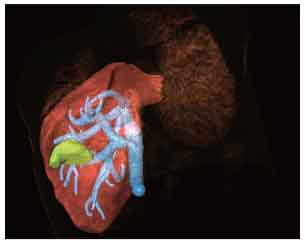

CT-Ultrasound Fusion in PCNL

3D CT reconstruction

HEPATOLOGY

Liver tumor ablation, ultrasound-guided ERCP, pancreatic cancer biopsy.